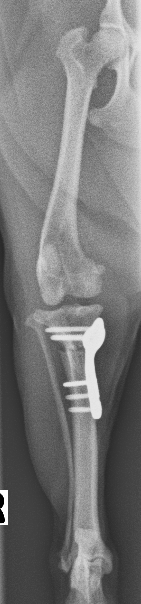

上画像は手術を実施した後の、術後X線画像です。脛骨近位を半円状に骨切りし、プレートで固定するTPLOと呼ばれる術式になります。計算された角度になる様、骨を回転させることで力学的な変化を起こし、膝関節を強固に安定させます。